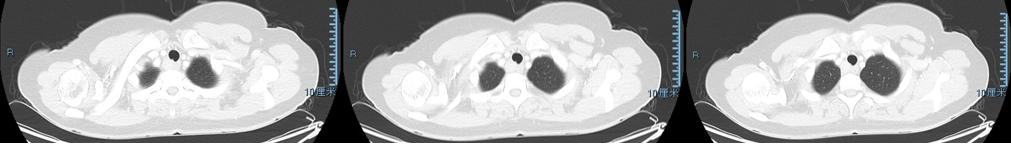

2019年感冒后咳嗽,查CT(图4)提示双肺斑片渗出影及索条影,左肺为著,气管右后方高密度实变影密度减低,囊腔较前明显增大。经抗感染、止咳、激素治疗后,肺部渗出影吸收。

图4 胸部CT(2019年):气管右后方囊腔较前增大,左肺渗出及索条影

2020年11月复查CT(图5):

图5 胸部CT(2020年11月):气管右后方高密度结节影

2021年4月感冒后咳嗽就诊当地医院,查胸部CT(图6):气管右后方见实性高密度结节影,突出气管腔内,左肺上叶胸膜下斑片状渗出影。

图6 胸部CT(2021年4月)气管右后方高密度结节,左上肺胸膜下少许渗出